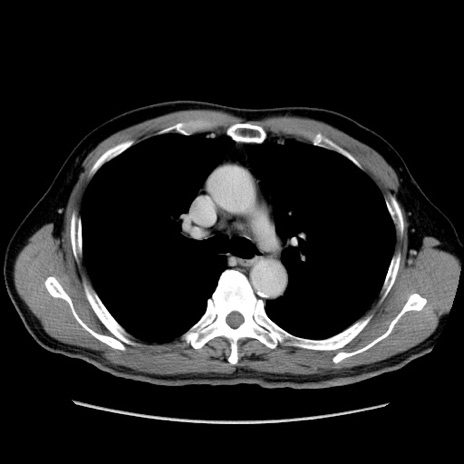

症例34(横断像)

【症例】60歳代 男性

【主訴】右鼠径部膨隆

【現病歴】1年程前より右鼠径部膨隆あり。自己にて還納可能だったため放置していた。3時間前より右鼠径部の脱出を認め、還納困難となり受診。

【身体所見】右鼠径部に小児頭大の膨隆あり。弾性硬であり、用手還納は困難。左鼠径部にも膨隆を認める。脱出はなし。